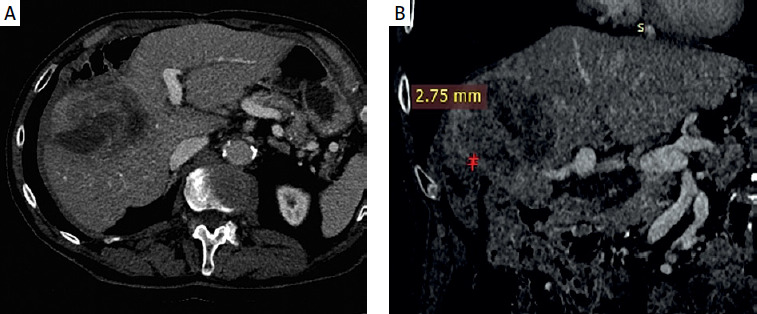

After multidisciplinary review, the decision to perform ablative RL with Y-90 resin microspheres (SIR-Spheres) was made. Pre-treatment work-up was performed and a dose of 500 Gy was planned for the tumor based on the partition model. Post-treatment dosimetry, performed using MIM Sureplan software, confirmed a mean absorbed dose of 463 Gy to the tumor, 215 Gy to the 5 mm margin, and 122 Gy to the 10 mm margin (Figure 2).

Figure 2

MIM software dosimetry analysis. Red arrow indicates absorbed radiation dose on post-Y90 PET/CT imaging, demonstrating its proximity to the colon